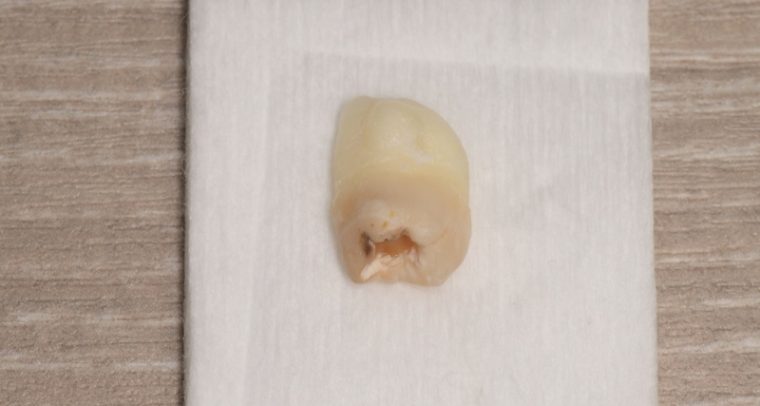

CASE 11

| 年齢・性別 | 33歳・男性 |

| 主訴 | 左上下親知らず抜きたい |

| 抜歯期間 | 30分 |

| 抜歯費用 | 約2,500円(保険内) 別途CT撮影で3,000円 (2022年7月現在) |

| 抜歯内容 | 左上下の親知らず抜歯 |

| 治療方針 |

初めに右下の奥歯が痛いとのことでご来院されました。 右下の親知らずと7番目の歯がカリエスになっていたため、まずは右下の親知らず抜歯と7番目の感染根管治療を行いました。左上下の親知らずもカリエスになっているため、今回抜歯を行いました。 |